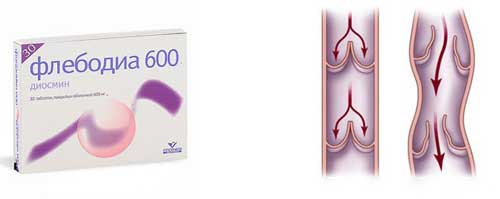

Флебодиа

Повышает устойчивость капилляров, снимает воспалительные процессы, восстанавливает кровообращение. Часто используется в составе комплексного лечения геморроидальных узлов и венозной недостаточности.

- Элементы, основанные на наличии взаимозаменяемых по воздействию на организм одного или нескольких идентичных активных веществ. Диосмин и гесперидин являются ключевыми активными ингредиентами. Препараты, содержащие микронизированную очищенную фракцию флавоноидов, считаются наиболее эффективными при различных формах заболеваний сосудов.